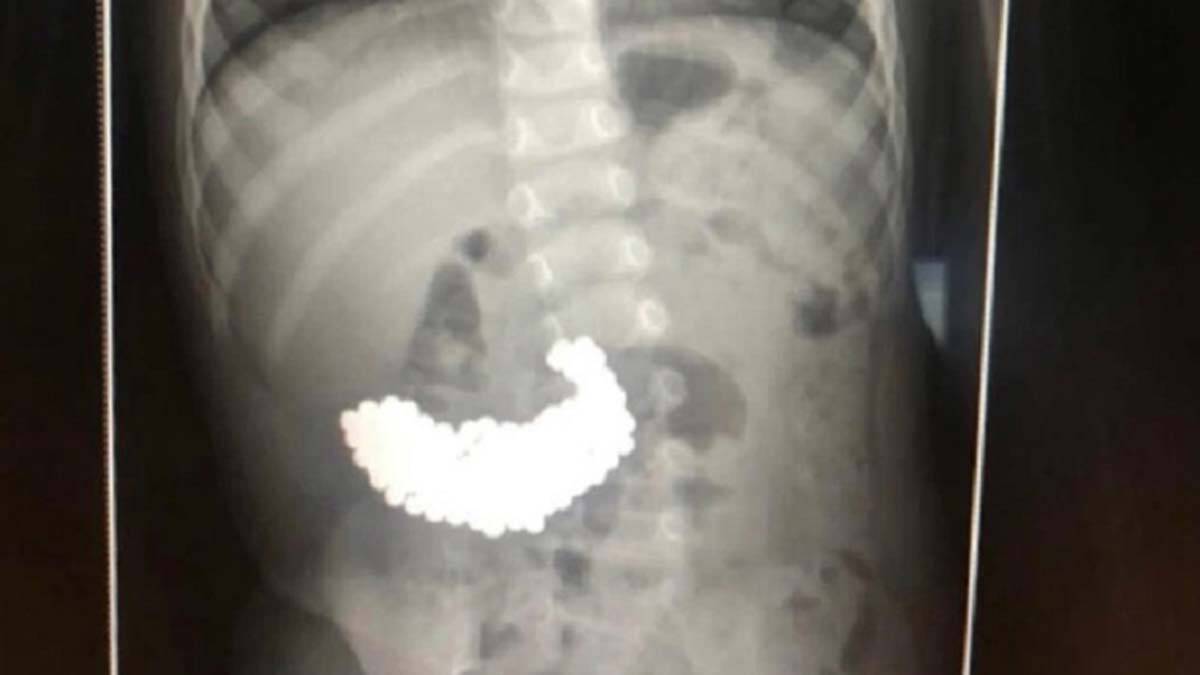

Rusya’nın başkenti Moskova‘da 2 yaşındaki çocuk ailesinin haberi olmadan neodyum adı verilen stres bilyeleri olarak da bilinen 209 adet mıknatıs topunu yuttu. Birkaç gün sonra çocuğun dışkısının siyah olduğunu fark eden aile doktora başvurdu. Hastaneye götürülen çocuğun röntgeni çekildi. Röntgende çocuğun midesindeki renkli mıknatıs topu ortaya çıktı.

Yapılan ameliyatta çocuğun bağırsaklarından 209 adet mıknatıs topu çıkarıldı. Ameliyatın 2 saat sürdüğünü ifade eden doktorlar, çıkarılan mıknatıs toplardan bazılarında mide zarını delebilecek keskin kenarlar oluştuğu ifade edildi. İki yaşındaki bebeğin mıknatıs toplunu 2 ay önce yuttuğu belirtilirken, sağlık durumunun iyi olduğu belirtildi.